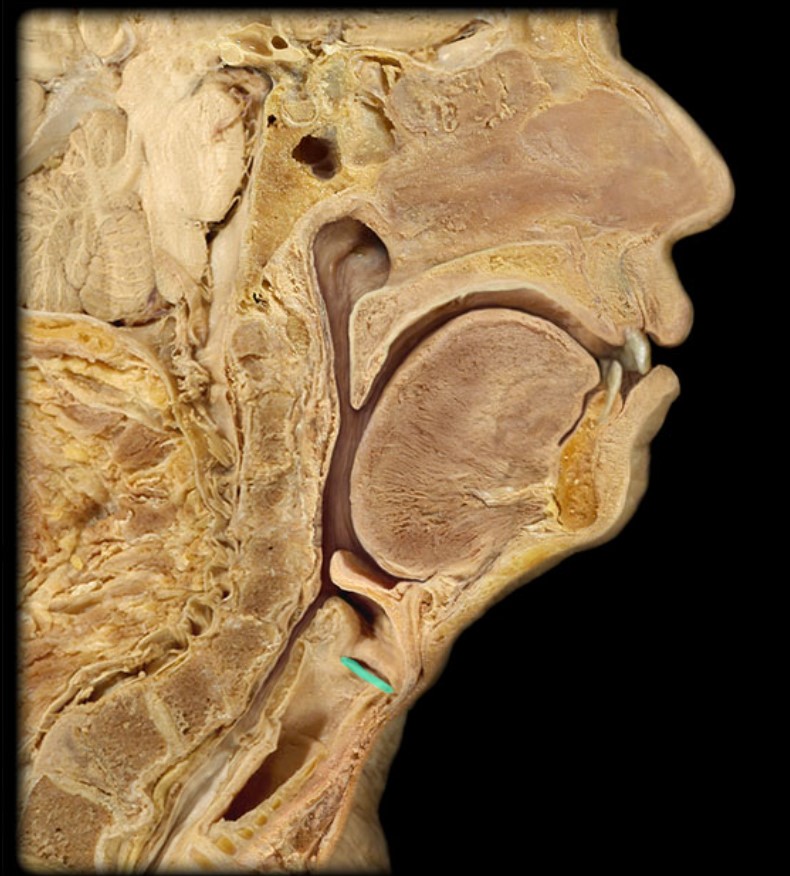

Anatomy 5 - Bifurcated Skull

29 Terms

1

New cards

Thyroid Gland

(Donor Only)

2

New cards

Atlas

3

New cards

Vertebral Artery

(Donor Only)

4

New cards

Nasal Septum

(Donor Only)

5

New cards

Esophagus

6

New cards

Trachea

7

New cards

Vocal Fold

8

New cards

Epiglottis

9

New cards

Hyoid

10

New cards

Mandible

11

New cards

Mylohyoid

12

New cards

Geniohyoid

13

New cards

Genioglossus

14

New cards

Lingual Tonsil

15

New cards

Palatine Tonsil

16

New cards

Uvula

17

New cards

Soft Palate

18

New cards

Palatine Bone

19

New cards

Maxilla

20

New cards

Pharyngeal Tonsil

21

New cards

Auditory Hiatus

22

New cards

Torus Tubarius

23

New cards

Sphenoid Sinus

24

New cards

Inferior Nasal Concha

25

New cards

Middle Nasal Concha

26

New cards

Superior Nasal Concha

27

New cards

Nasal Vestibule

28

New cards

External Nares

29

New cards

Frontal Sinus